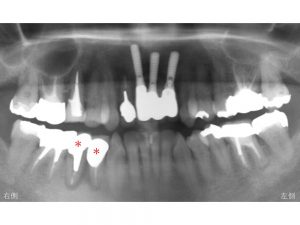

早速初診時のレントゲンからみてみましょう。

上顎前歯部のインプラント治療は以前に他の歯科医院で行なっていました。

患者様の主訴は下顎右側の奥歯の腫れと痛みです。

以下の*印の歯が歯根破折しており残すことが不可能であったため

抜歯と診断しました。